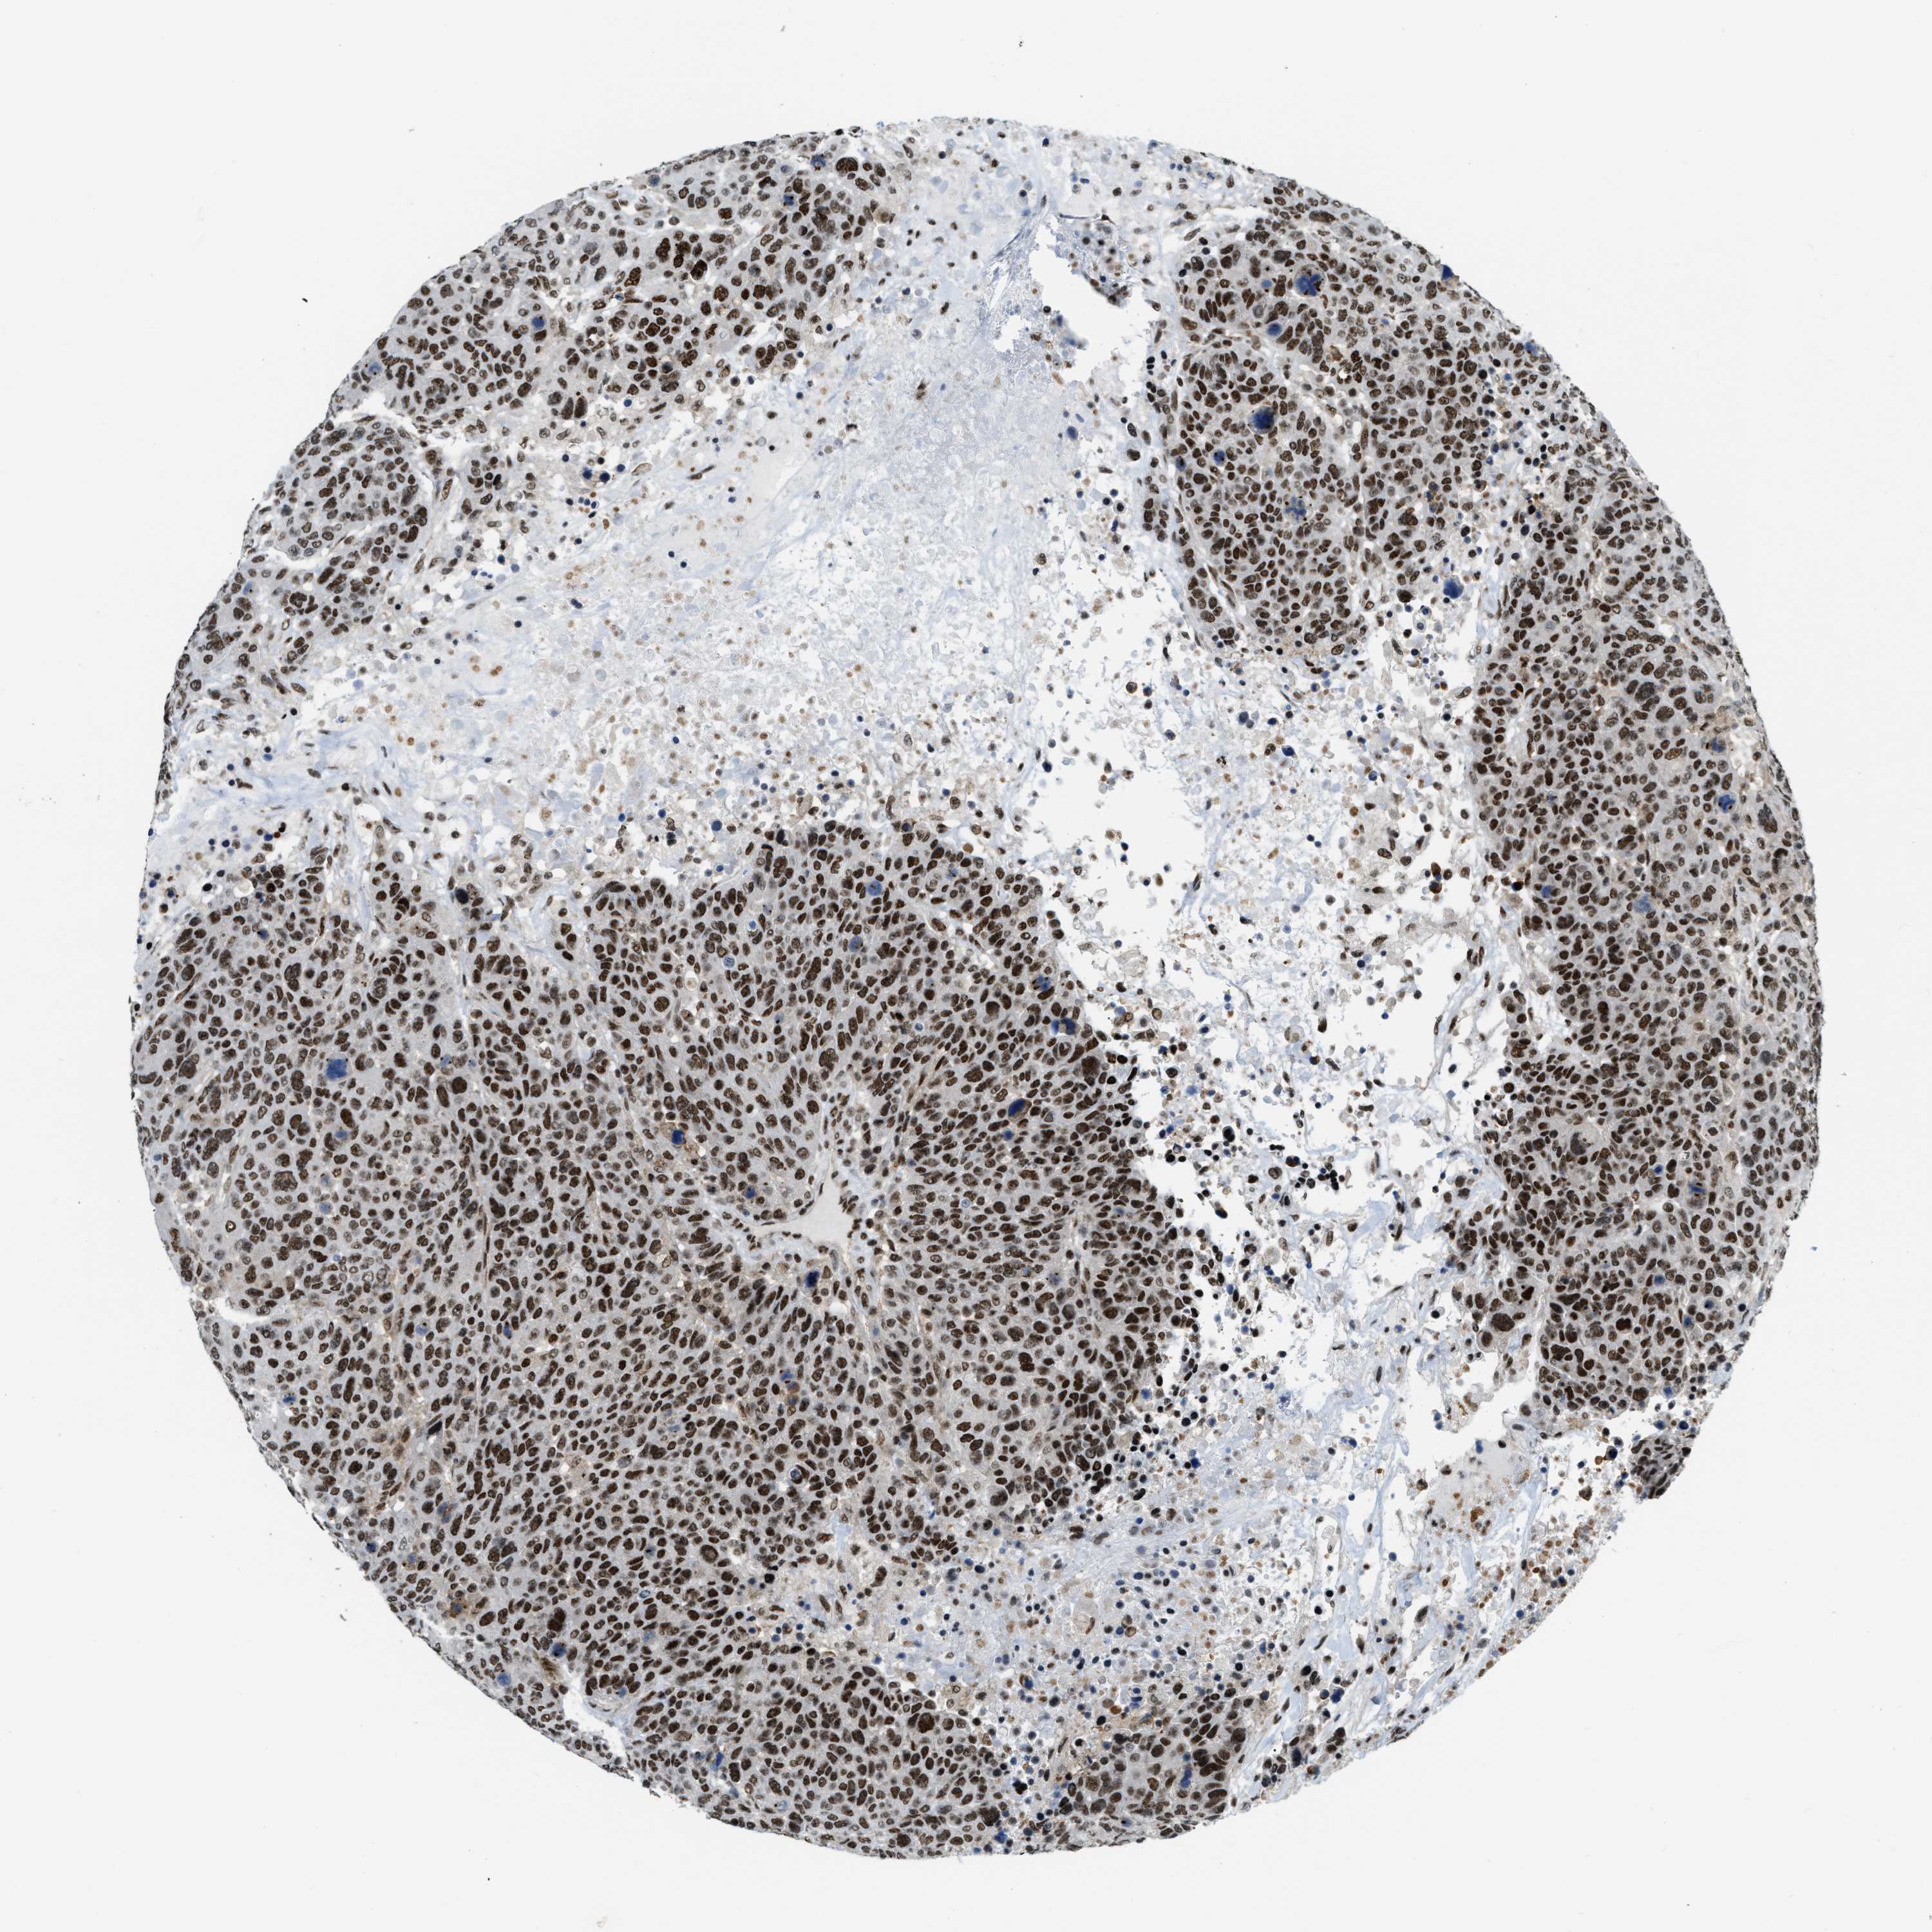

CANCER BREAST CANCER Show tissue menu

Breast cancer

Human cancer